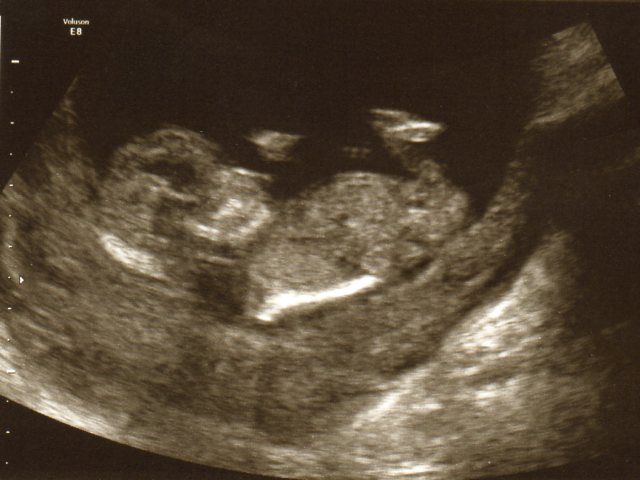

Compared to these 12 weeks + 5 Days pictures everyone has said BOY but looking more like a girl to me in 21 weeks.

Attachment 13163